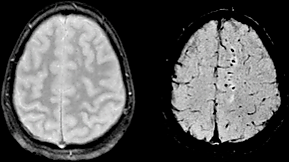

При диффузном аксональном повреждении головного мозга микроскопические мелкоочаговые кровоизлияния выявляются в мозолистом теле, полуовальном центре, верхних отделах ствола мозга. Клинически оно проявляется длительной комой, которая в большинстве случаев переходит в вегетативное состояние. Последнее характеризуется отсутствием корковой деятельности и длится месяцы и годы.

Дети с данным повреждением могут иметь нормальный или неспецифический срез КТ[1].